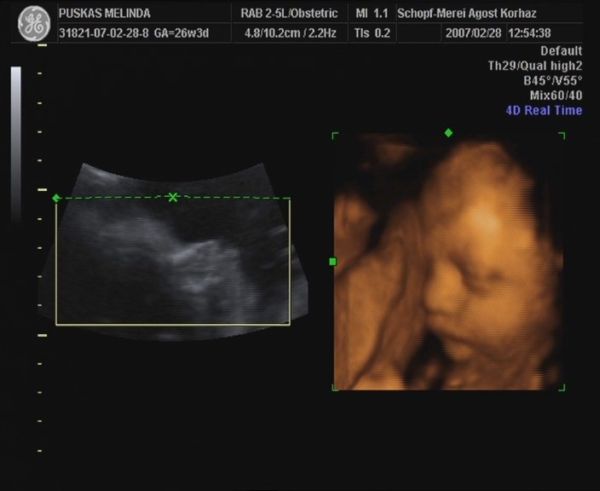

Ezt egy nagyon szép ajándék. Én is szeretnék képet látni a babóról.